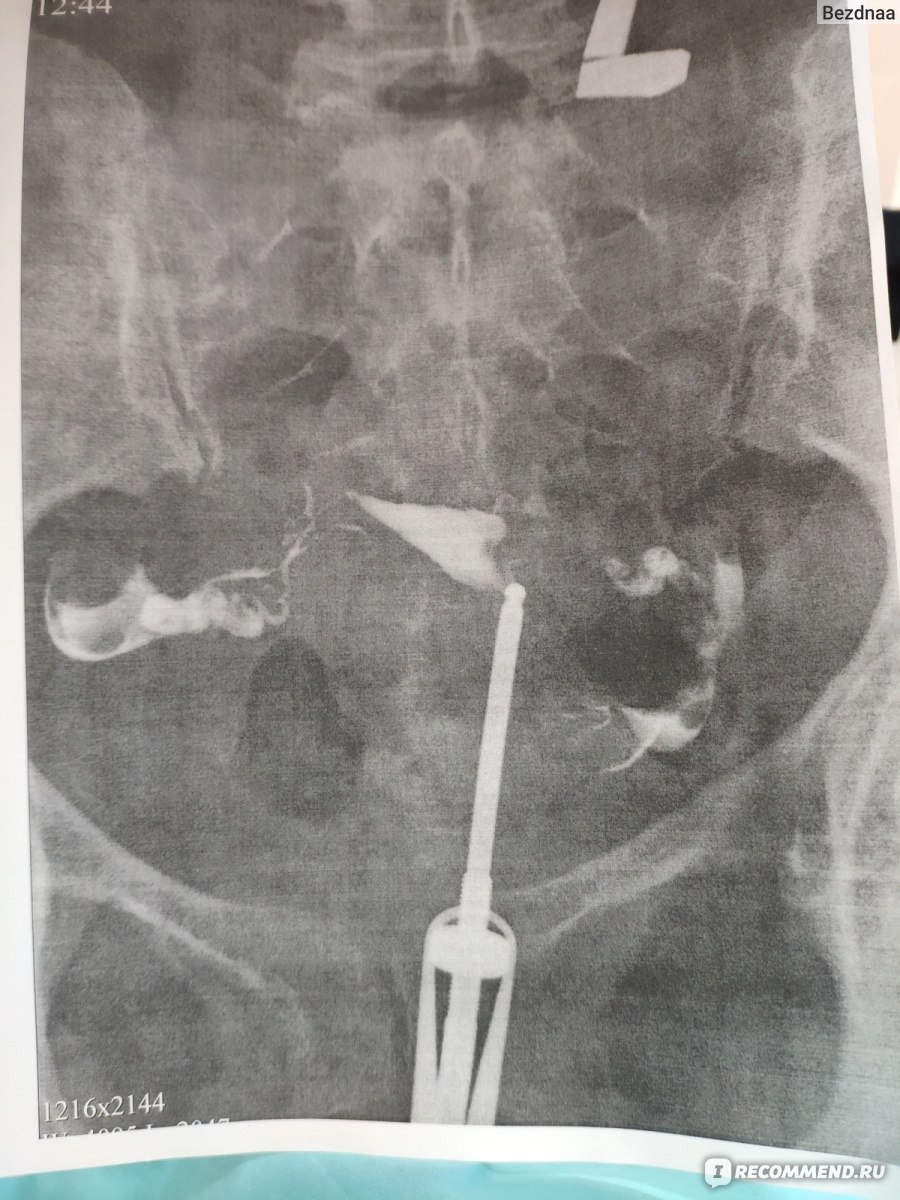

Гистеросальпингография: описание и фотографии